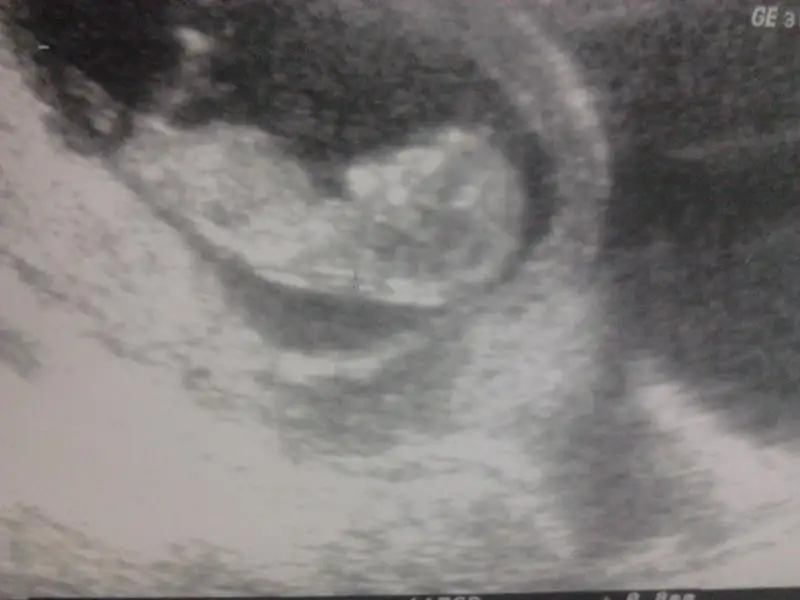

kızlar tecrübeli arkadaşlardan yorum rica ediyorum. doktorum%85-90 erkek dedi. henüz 12. haftamdayım. $2014-02-12 18.18.41.webp

kızlar tecrübeli arkadaşlardan yorum rica ediyorum. doktorum%85-90 erkek dedi. henüz 12. haftamdayım. Eki Görüntüle 977889

Cnm benim onceki sayfalari ben cok okudum...anladigim kadariyla senin sipa ilk bakista kiza benziyo cunki paralel ama nubu buyuk oldugu icin erkeye donenlerden diye anlatiyorlar boyle bebisleriiii...yani ben okuduklarimdan boyle oyrendimm.hem dk erkek demis cnm alisverisine basla artikkkk:nazar:

Paralel ama buyuk yani erkk